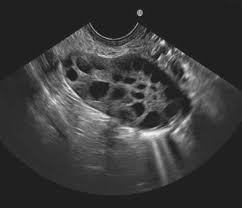

Lorsqu’une femme a des cycles menstruels “normaux”, elle produit chaque mois au cours de la phase folliculaire de son cycle, sous l’influence de l’hormone folliculo-stimulante, un follicule dominant appelé follicule de Graaf. Celui-ci va évoluer et devenir le plus gros, et libérera un ovocyte lors de l’ovulation. Pour les femmes atteintes du SOPK, ce processus est altéré car elle ne produit pas la bonne combinaison d’hormones. Au lieu d’être expulsé, le follicule se maintient dans l’ovaire pour former un “kyste”, l’accumulation de ces “kystes” ayant présidé au choix du nom de cette pathologie.

• des ovaires d’aspect polykystique.

Ovaire polykystique

L’importance de chacun de ces critères dans le tableau clinique du SOPK est sujet à débat. Ils peuvent notamment conduire à diagnostiquer une femme qui aurait des règles irrégulières et des ovaires d’aspects polykystiques mais pas d’excès d’androgènes. Or “la découverte d’une morphologie ovarienne polykystique chez des femmes ovulatoires ne présentant pas d’excès androgénique clinique ou biochimique peut être sans conséquence” (Dewailly D, Lujan ME, Carmina E, Cedars MI, Laven J, Norman RJ, et al., 2014). Autrement dit, il est tout à fait possible d’être atteinte du SOPK en présence d’une échographie tout à fait normale, tandis que des ovaires d’aspects polykystiques à l’échographie n’équivaudront pas nécessairement à un diagnostic de SOPK.